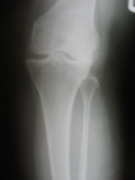

Knee Joints Case A

Knee Joint Replacement Knee Joint Replacement Knee Joint Replacement